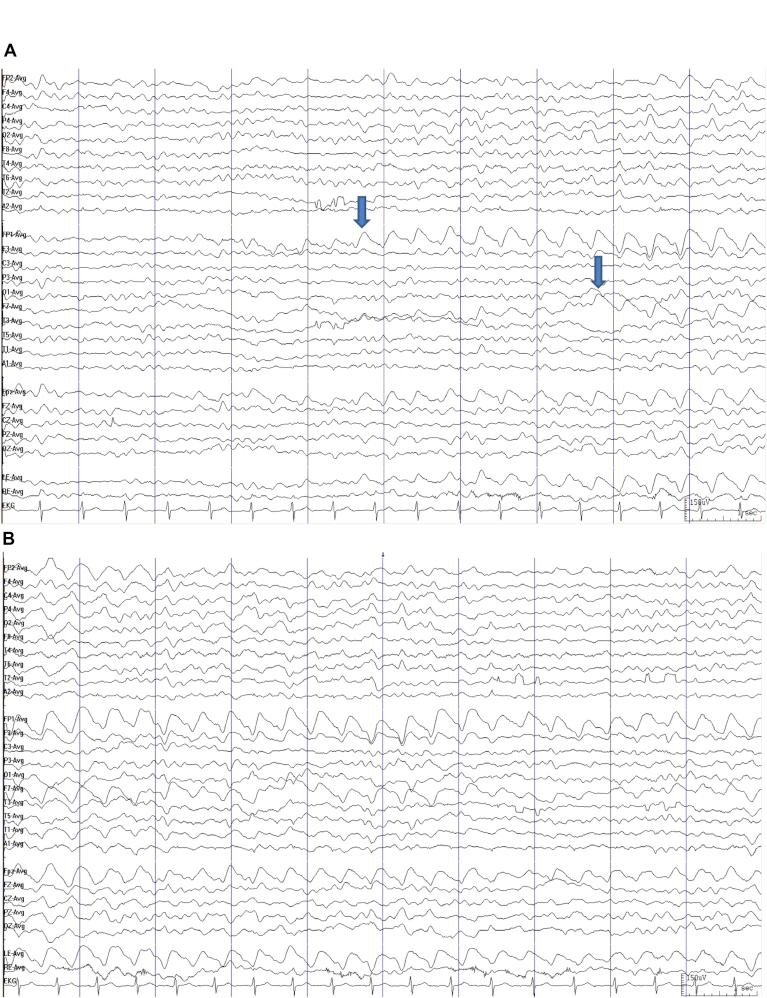

Moderate-to-severe traumatic brain injury (msTBI) can cause non-convulsive status epilepticus (NCSE). Electroencephalography (EEG) is employed as a diagnostic tool due to the non-specificity of clinical symptoms. This study aimed to identify clinical and EEG features related to NCSE in patients with msTBI.

This was a cross-sectional study. Suspected NCSE in msTBI was examined using EEG data collected in consecutive patients from January 2017 to December 2019 at Dr. Cipto Mangunkusumo Hospital, Jakarta. Diagnoses of NCSE were made based on clinical manifestations and EEG features using the modified Salzburg Consensus Criteria for NCSE (mSCNC).

Of the 39 msTBI patients, 19 were diagnosed with NCSE; only two fulfilled the definitive criteria, and the remaining were possible NCSE. Delirium and perceptual impairment were only found in NCSE, while psychomotor agitation was higher (12.8% 5.1% in NCSE non-NCSE). The most common EEG feature was rhythmic activity (>0.5 Hz) without fluctuation, which improved with anti-epileptic drug administration. The Glasgow Coma Scale (GCS) score at onset and at hospitalisation discharge was significantly lower in patients with NCSE. The lesions in NCSE mostly originated from the temporal lobe. Injury to the temporal lobe had a significant relationship with NCSE occurrence (p = 0.036, odds ratio 11.45 [95% confidence interval 1.17-111.6]).

Post-traumatic NCSE can manifest as an alteration in mental status that could lead to missed diagnosis. In this study, delirium, perceptual impairment, and psychomotor agitation were confirmed as NCSE using EEG. The most common discharge originated from the injured temporal lobe, and this site was a significant factor associated with NCSE in patients with msTBI.